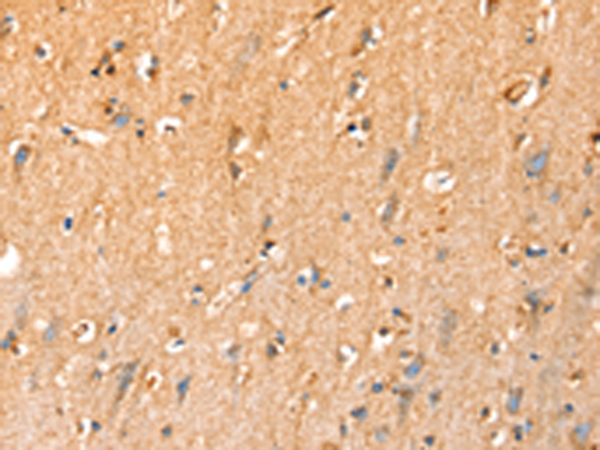

分类: 科研抗体货号: P05301别名: PHC; PTP; OK/SW-cl.48应用: IHC反应种属: Human, Mouse, Rat

分类: 科研抗体货号: P05340别名: MSK; SIK; SNF1LK应用: IHC反应种属: Human, Mouse, Rat